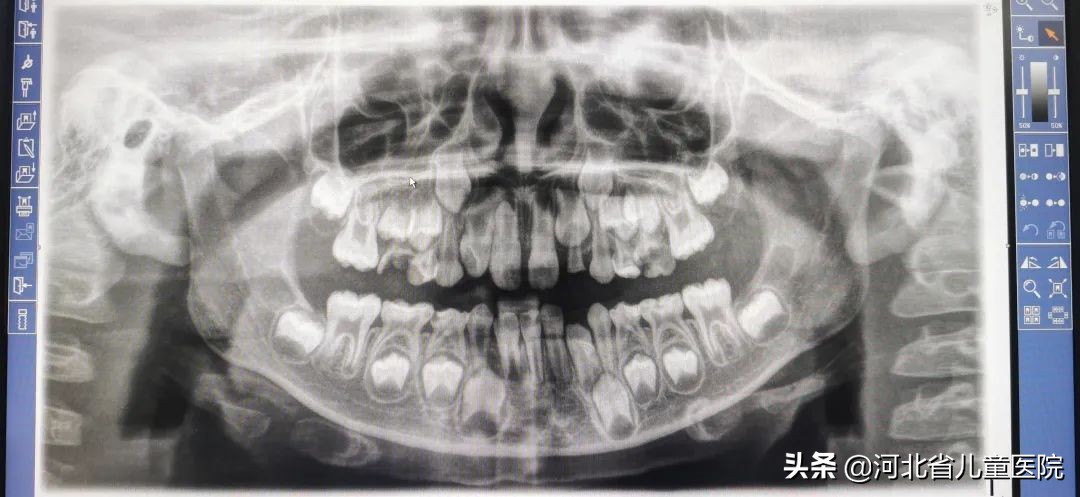

7岁的患儿在拍摄X线片时发现上颌埋伏多生牙一颗。经CT检查,多生牙位于右上中切牙后方根中1/2至根尖部,多生牙呈锥形倒置位。完善术前各项检查,检查结果正常,于手术室行全麻下多生牙(阻生)拔除术,手术治疗成功,患儿复苏良好并在家属陪同下当日离院。